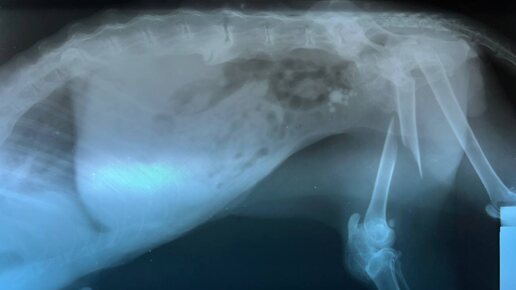

Переломы у животных — это нарушение целостности кости, которое может произойти из-за травмы, падения, ДТП или на фоне заболеваний (остеопороз, опухоли). Такие повреждения требуют быстрой диагностики и правильного лечения, чтобы избежать осложнений. Ветеринар проведёт: Переломы у животных – серьёзная травма, требующая немедленной помощи...